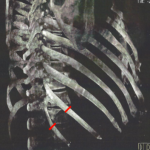

Plastic Surgery Case Study – The Location of The Pleura in Rib Removal Waistline Narrowing Surgery

Background: One of the considerations in rib removal surgery is the location of the lung. Anatomically they extend from just above the clavicle down to the 6th rib in the front and the 10th rib in the back…which is where we are most interested in rib removal surgery. It is also relevant to note that Read More…